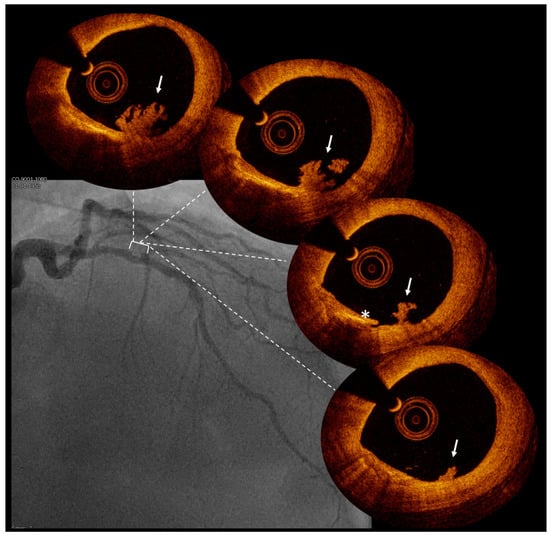

Figure 2.

Intracoronary thrombus detection by optical coherence tomography. Legend: coronary angiography of a patient presenting with minor anterior non-ST elevation myocardial infarction without obstructive coronary artery disease. Optical coherence tomography showed the presence of a thrombus (arrow) near a small dissection (*), giving proof of an acute coronary event.